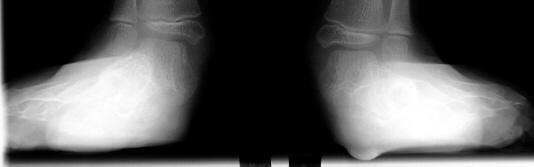

A six year old female followed for spastic quadriplegic cerebral palsy presented with increasing difficulty with ambulation secondary to bilateral hamstring tightness and progressive planovalgus deformity of the feet. Examination revealed a small thin six year-old female with severe bilateral planovalgus deformity which has become a progressive problem. While walking, the bilateral planovalgus deformity causes her to bear weight on her medial midfoot.

On weight bearing x-rays the talocalcaneal angle is 44 degrees and talonavicular angle is 40 degrees. This indicates that surgery is definitely indicated.